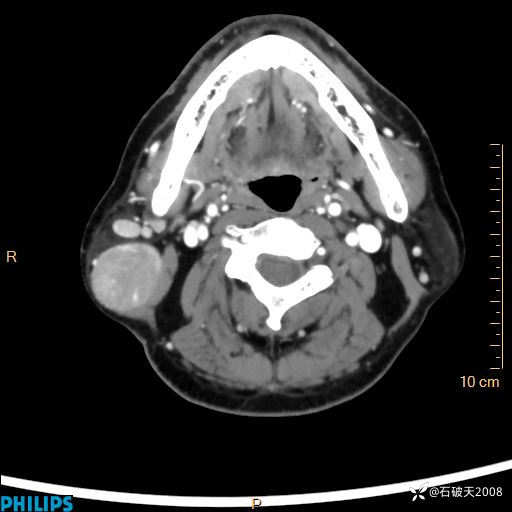

MIP